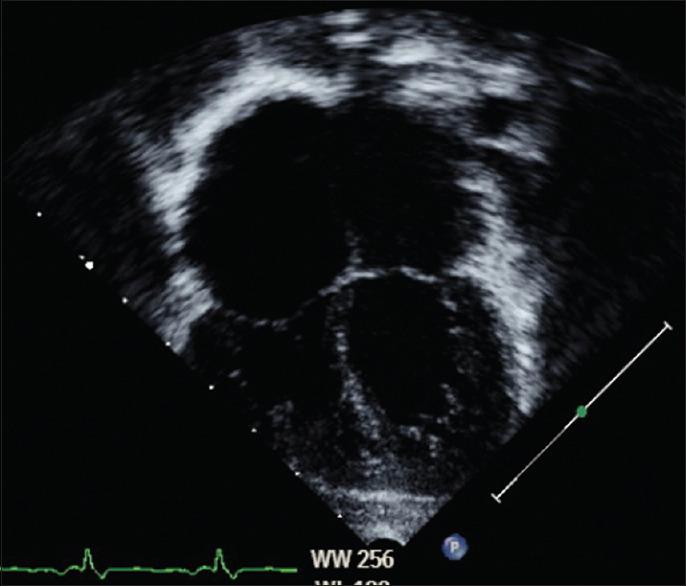

This is a case of a 3-year-old child who presented with long-segment tracheal stenosis (LSTS) and complex congenital cardiovascular disease for surgical intervention. The ideal operation for this child will include slide tracheoplasty and multiple cardiac lesion repairs. However, the low birth weight and extremely young age present a dilemma as to whether to perform total repair simultaneously or in stages. Age and weight by which the first surgical procedure was done, cardiovascular abnormality details, preoperative respiratory support, preoperative tracheobronchomalacia, cardiopulmonary bypass, the complexity of the surgery, and preoperative extracorporeal membrane oxygenation support are known to be predictive factors of long-term outcomes. Comparative studies between simultaneous and staged operations have shown that it is best to manage children with LSTS and complex cardiovascular anomalies in stages.

这是一例3岁儿童,因长段气管狭窄(LSTS)和复杂先天性心血管疾病接受手术干预。该患儿的理想手术包括滑动气管成形术和多处心脏病变修复。然而,低出生体重和极低年龄使手术面临是同期进行完全修复还是分期修复的两难困境。已知首次手术时的年龄和体重、心血管异常细节、术前呼吸支持、术前气管支气管软化、体外循环、手术复杂性以及术前体外膜肺氧合支持是长期预后的预测因素。同期手术和分期手术的对比研究表明,对于患有LSTS和复杂心血管畸形的儿童,最好采用分期治疗。